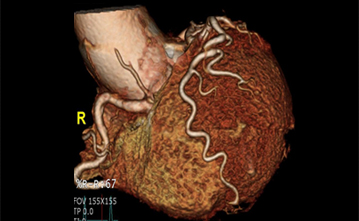

경피적 심혈관조영술과 같이 침습적이며 입원을 하여 시행하는 검사외에 외래에서 검사할 수 있는 CT 혈관 촬영술이 있습니다. 이는 6시간 정도의 금식이 필요하며, 다른 장기의 CT촬영과 방법이 같습니다. 조영제를 사용해서 혈관을 보는 검사방법이여서, 신장기능과 같은 기본 혈액검사의 결과를 확인 후 조영제를 정맥주사를 통해 주입하여서 그림과 같은 관상동맥의 구조와 협착정도를 눈으로 확인할 수 있게 됩니다. 입원의 절차도 필요없고, 동맥천자와 같은 침습적인 방법도 시행하지 않는다는 간편성은 있지만, 병변의 진단만 가능한 검사이며 심각한 협착이 발견된다면, 침습적 혈관조영술이 추가 필요하게 될 수도 있습니다.